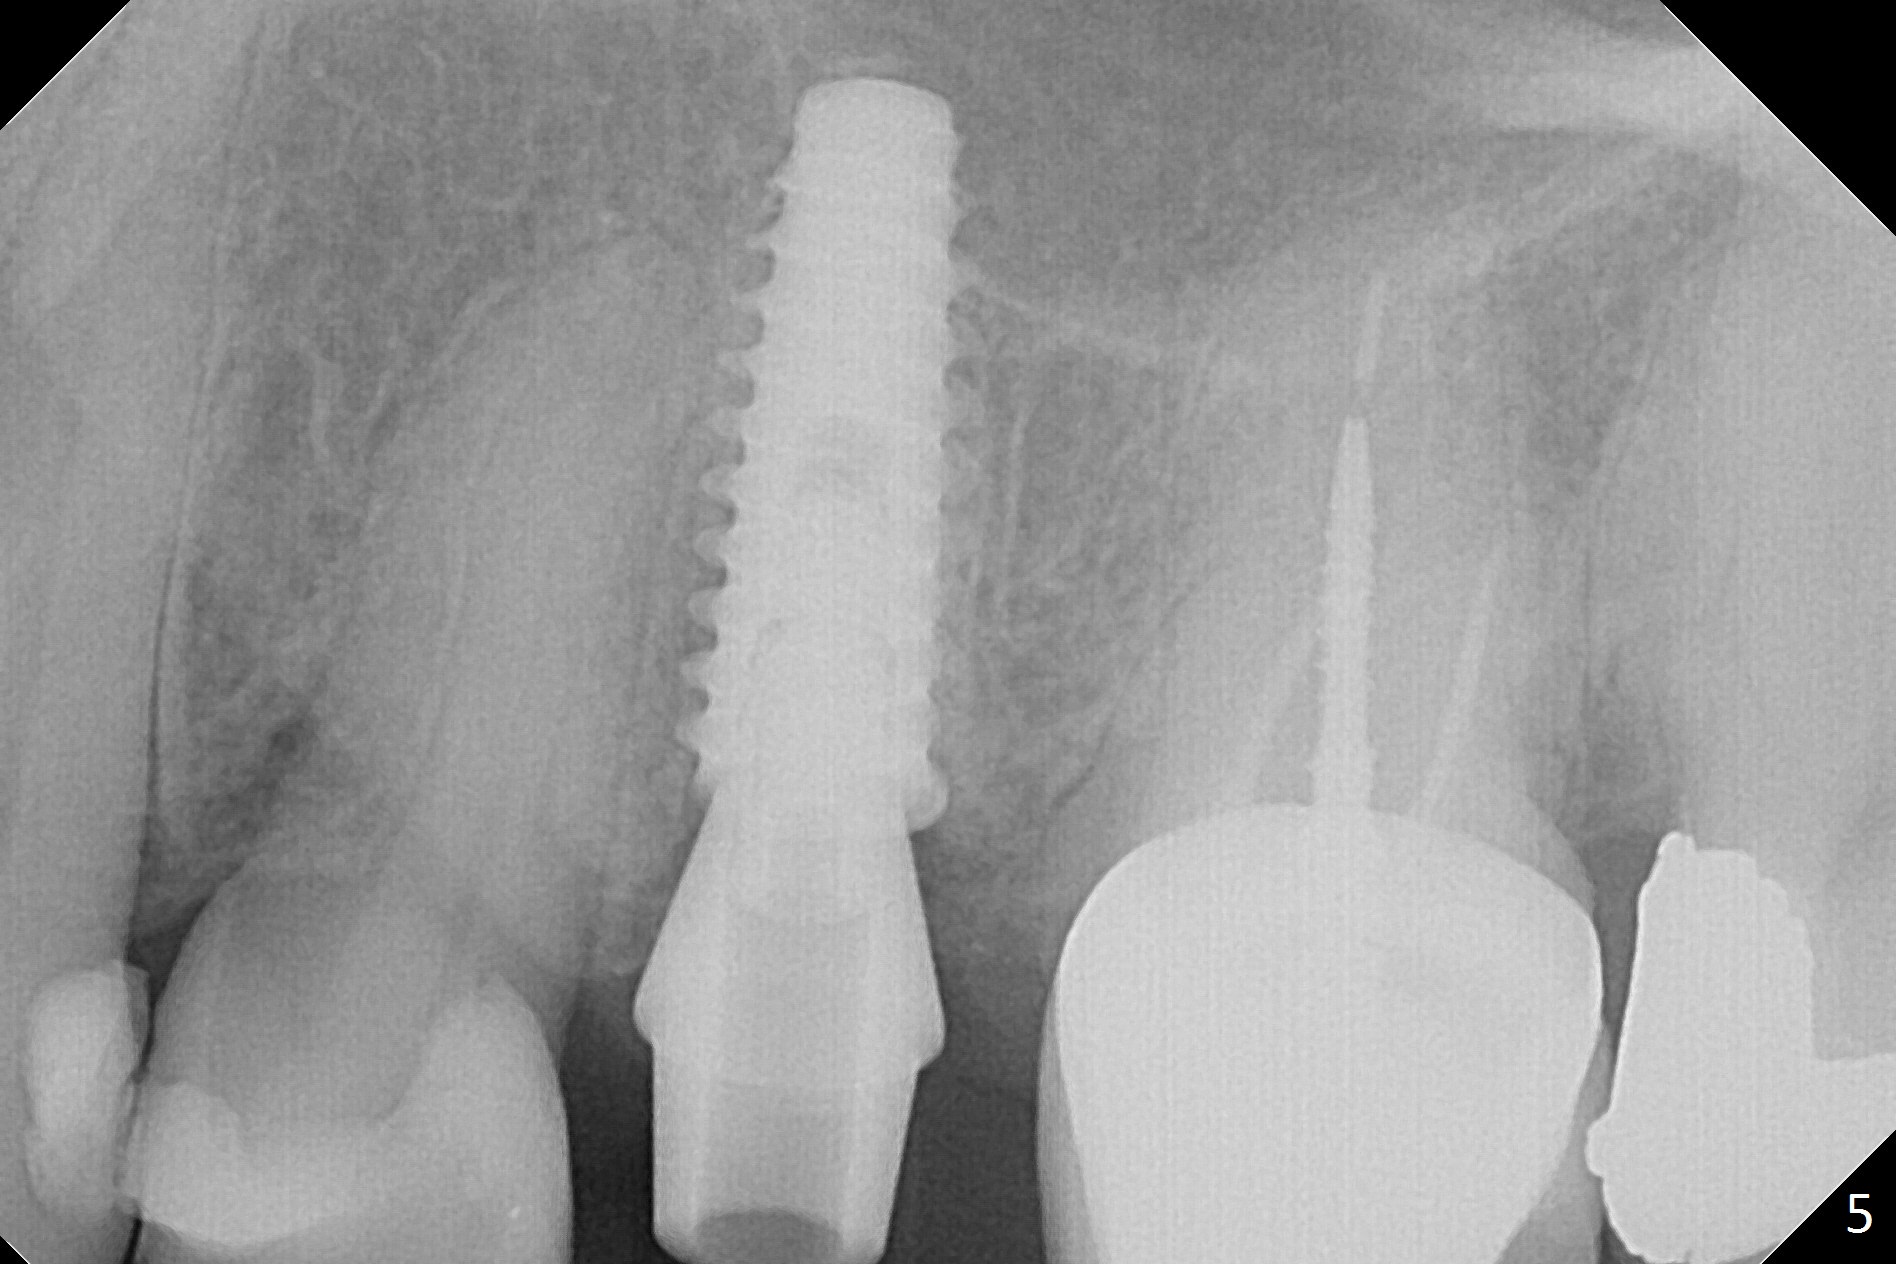

Since the apical native bone is limited at #13 after extraction, no PA is taken until a 4x11 mm dummy implant is placed after 1.6 mm and 3.3 mm drills for 13 mm (Fig.1). After using Lindamann bur to move the osteotomy distal and reusing 3.3 mm drill, the trajectory of a 4.5x11 mm IBS dummy implant improves (Fig.2,3 with low stability). When the implant is removed, the buccal portion of the socket is found to be perforated (Fig.4 P). Although the reason for the perforation is unknown, it is repaired by insertion of a piece of PRF plug, followed by allograft. #1 and 2 in Fig.4 represent the 1st and 2nd osteotomies, as shown in Fig.1 and 2, respectively. The trajectory of the final 5x13 mm implant is acceptable (Fig.5-7, different angulations), so is insertion torque (45 Ncm). After placing a 5.5x4(4) mm abutment, an immediate provisional is fabricated (Fig.8 P) with occlusal clearance (*). The interdental papillae remain in place 12 days postop (Fig.9 *). There is no sign of postop sinus infection. The provisional is loose 18 days postop; the abutment is changed to 5x4(3) mm (Fig.10). It is difficult to catch the mesial margin of the abutment for impression 4 months postop, due to poor oral hygiene and the short cuff (3 mm, Fig.11). The appointment for impression is rescheduled with emphasis on oral hygiene and no wearing the provisional for a few days prior to next appointment. Bone has grown into the space between the 1st and 2nd threads 5 months post cementation (Fig.12) and the bone is normal, solid and dense 2 years 11 months post cementation (Fig.13 >). There is mesial open margin of the tooth #14 (Fig.13,14 *).